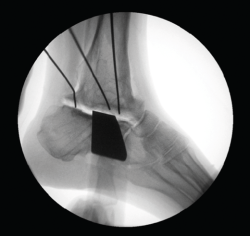

Figura 5. Control por radioscopia del aloinjerto.

- Tallado del injerto de manera intraoperatoria (Figuras 4 y 5).